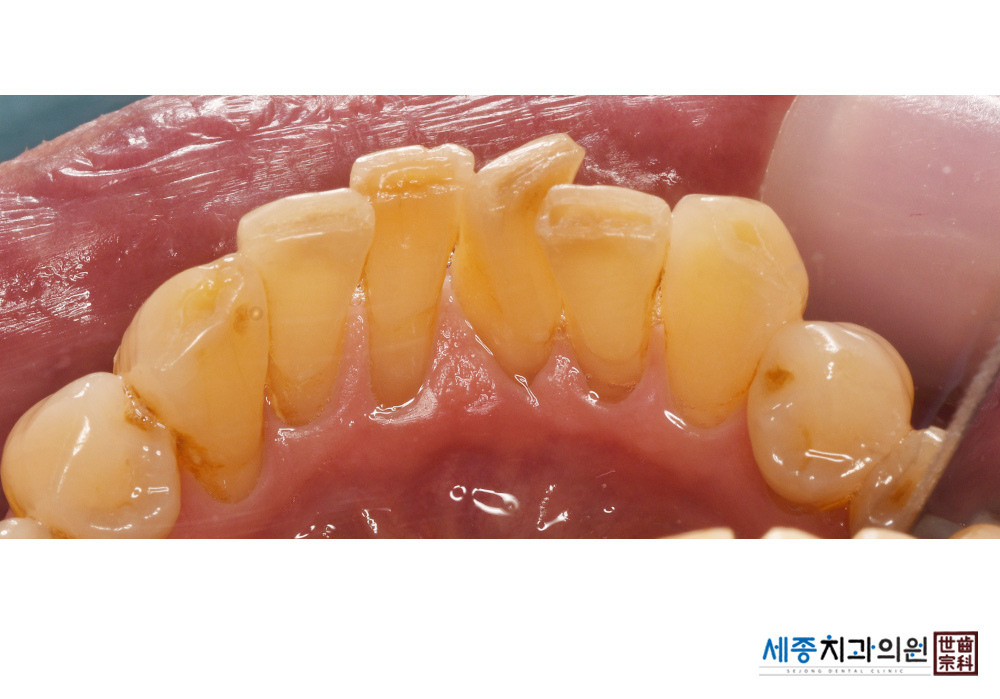

[스케일링] 치주질환 예방 스케일링

치료전 : 2020-02-04

치료후 : 2020-02-04

가글마취&저주파 스켈러를 사용한 스케일링